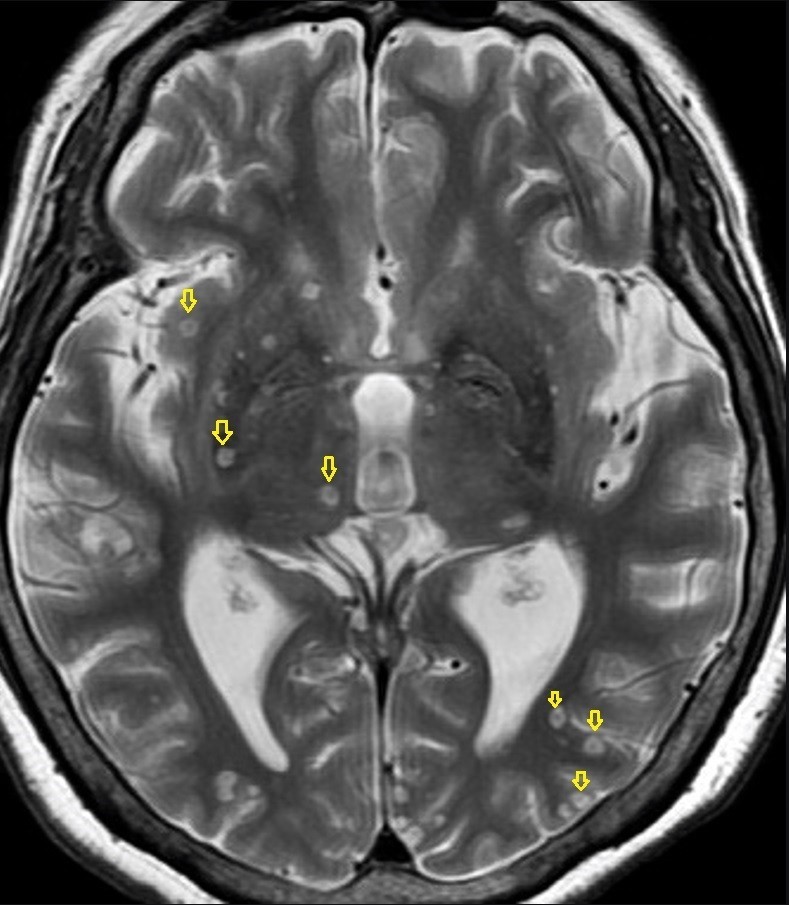

磁振造影檢查顯示,腦部有許多小黑點。(台北慈濟醫院提供)

他也說,過往診斷豬囊尾蚴蟲的方式是取出部分腦組織化驗,不僅技術困難且有傷害腦組織的風險,直到2017年國際放射線醫學會修正診斷準則,只要腦部磁振造影影像顯示有小於2公分的圓影,裡面有小黑點或沒有小黑點,但顯示有大型病灶,且有生食豬肉生活史者,便可直接診斷,盡快給予有效的抗寄生蟲藥物治療。